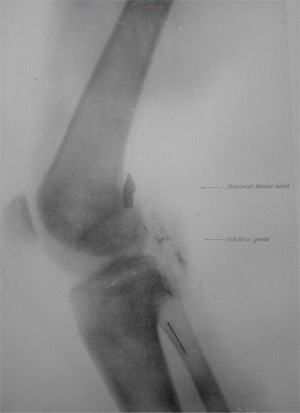

The new high-velocity bullets produced only a small entry wound and often passed straight through the body. The older gaping entrance wounds were no longer seen and army surgeons found that exploration for bullets was often more harmful than careful observation. The introduction of radiography helped in the development of modern war surgery by locating retained bullets. Although the early x-ray tubes were very fragile, the apparatus available before 1900 could detect fractures and foreign bodies.

There was a long journey to the base hospital at Rawalpindi with transport being slow so the surgeons therefore treated wounds earlier and nearer to the front line. Walter Beevor, a regimental surgeon with the Coldstream Guards, examined 200 cases with x-ray on the Tirah plateau and later took further x-rays in the hospital at Rawalpindi. The examinations included the leg of Gen. Woodhouse whose leg wound had failed to heal, and some weeks later Beevor was able to show the retained bullet. Beevor made a presentation to the United Services Institution in May 1898, which signaled the introduction of field x-ray units into the British Army. It is interesting that Walter Beevor had purchased his apparatus at his own expense.

One hundred and twenty-one wounded were transferred to Abadeih, and in 21 cases the conventional approach could not find a bullet. In 20 of these cases, an accurate diagnosis was made using x-ray, and in the final case the patient was too ill to be examined. Battersby concluded radiography prevented suffering by unnecessary probing of the wound, and in addition to simple radiography he used the cross-thread localization device of James Mackenzie Davidson.

Following injury, the casualty was sent to a regimental aid post, then by field ambulance to the casualty clearing station, some miles behind the front. If radiography was required, then the patient was transferred to the x-ray room. Most of the x-ray work was in the detection of retained bullets, and a simple apparatus was used. The stretcher with the patient was placed on supports above a movable x-ray tube. The patient was rapidly fluroscoped, and using a parallax technique with tube movement, the depth of the foreign body and its relation to the point of entry could be determined quickly and a written report issued. The apparatus was powerful enough to diagnose thoracic injuries, and the use of stereoscopy was common.